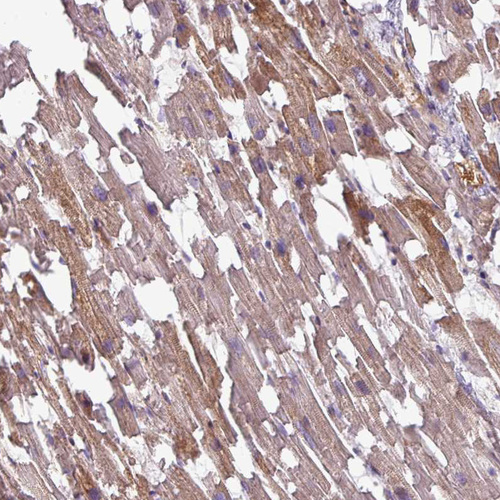

Immunohistochemical staining of human heart muscle shows moderate cytoplasmic positivity in cardiomyocytes.